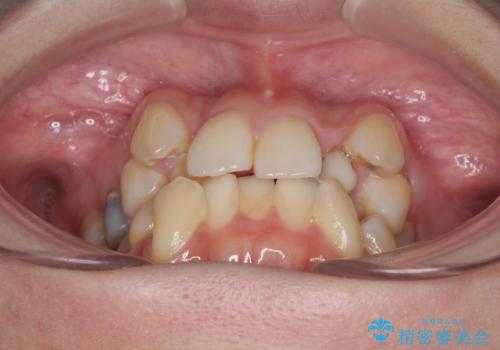

- 結婚式に向けて、八重歯と虫歯で変色した歯を改善したいとのことで来院された患者様です。

上下ともにデコボコが強いため、上下顎左右小臼歯各1歯を抜歯して歯列を整えることとしました。

大きな虫歯が認められた歯は、矯正治療後にオールセラミッククラウンにて補綴治療を行うこととしました。